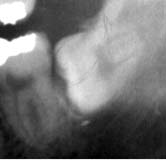

初診時 パノラマ 「8 拡大図 抜去 術式

下顎左側に埋伏した智歯が認められる

35歳 女性

レントゲンで見る以上に骨が歯冠部分を覆っている 周囲骨削除の上、歯冠カット

主訴は、|12の腫脹。

初診時口腔内およびX線所見:

主訴の|12は、歯根中央部の崩壊に伴う炎症が存在した。それ以外にも6|の 根尖病巣による腫脹が認められたが、清掃状態は比較的良好で、「8の埋伏を認めるも 臨床症状はないように思われた。

処置および経過:

上顎の治療を終了後メインテナンスに移行して約1年経過したころより、「8部の疼痛を訴えるよ うになった。

「7遠心の歯肉腫脹を起こすに至って、切開・排膿を試みると同時に探針で「8の埋伏状態を探った が、歯冠を触知することが難しくほとんど"完全埋伏歯"に近いことが疑われた。 ほとんど"完全埋伏歯"であることから、当初は、「7遠心根に歯石が沈着して起こした炎症を 疑ってしばらく経過を観察することとしたが、炎症は軽快することなく再び排膿を伴う腫脹を 起こしたことを契機として抜歯を決断。

歯冠のほんの一部が露出した埋伏歯であることから、周囲骨を大きく削合して、通例に従って 歯冠カットのうえ抜歯を行った。術後の経過は良好。

考察:

歯肉の上に顔を出した埋伏歯はほとんど抜歯の対象となるが、骨内に完全に埋伏した 智歯は炎症を起こさない限り抜歯の対象となることは少ない。しかし、わずかといえども 歯肉の隙間を介して口腔内と交通した場合には炎症を起こすことも決して稀なことではない。 ひとたび炎症を起こすようになった智歯はいつか抜歯しなくてはならない運命にあるといえる。

本症例の場合は、周囲骨の削合に結構時間を要したが、幸いにも歯根形態が単純であった ので比較的容易な症例であった。